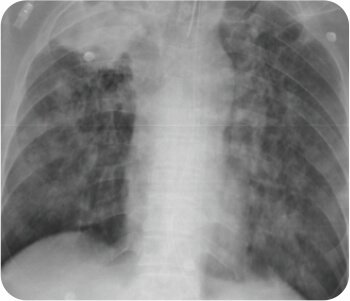

Pre procedure X ray

CT chest with thoracic angiogram revealed bilateral cavitary lesion with hypertrophied collateral arteries predominantly supplying the right upper lobe cavity. FOB done showed active bleeding from right upper lobe bronchus.